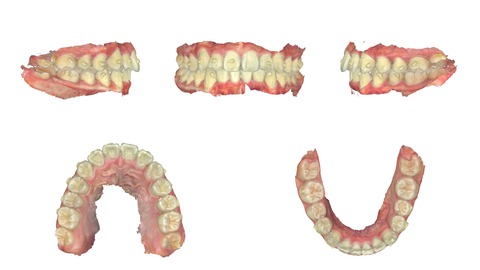

インビザラインで治療を終了した10代の患者さんのケースをご紹介する。

2024年4月5日に治療をスタートした。

内側に引っ込んだ歯を治したいという希望だった。

上の歯。前歯に内側に引っ込んだ歯がある。

下の歯にも同様に引っ込んだ歯がある。

横から見ると少し前歯が出っ歯気味になっている。